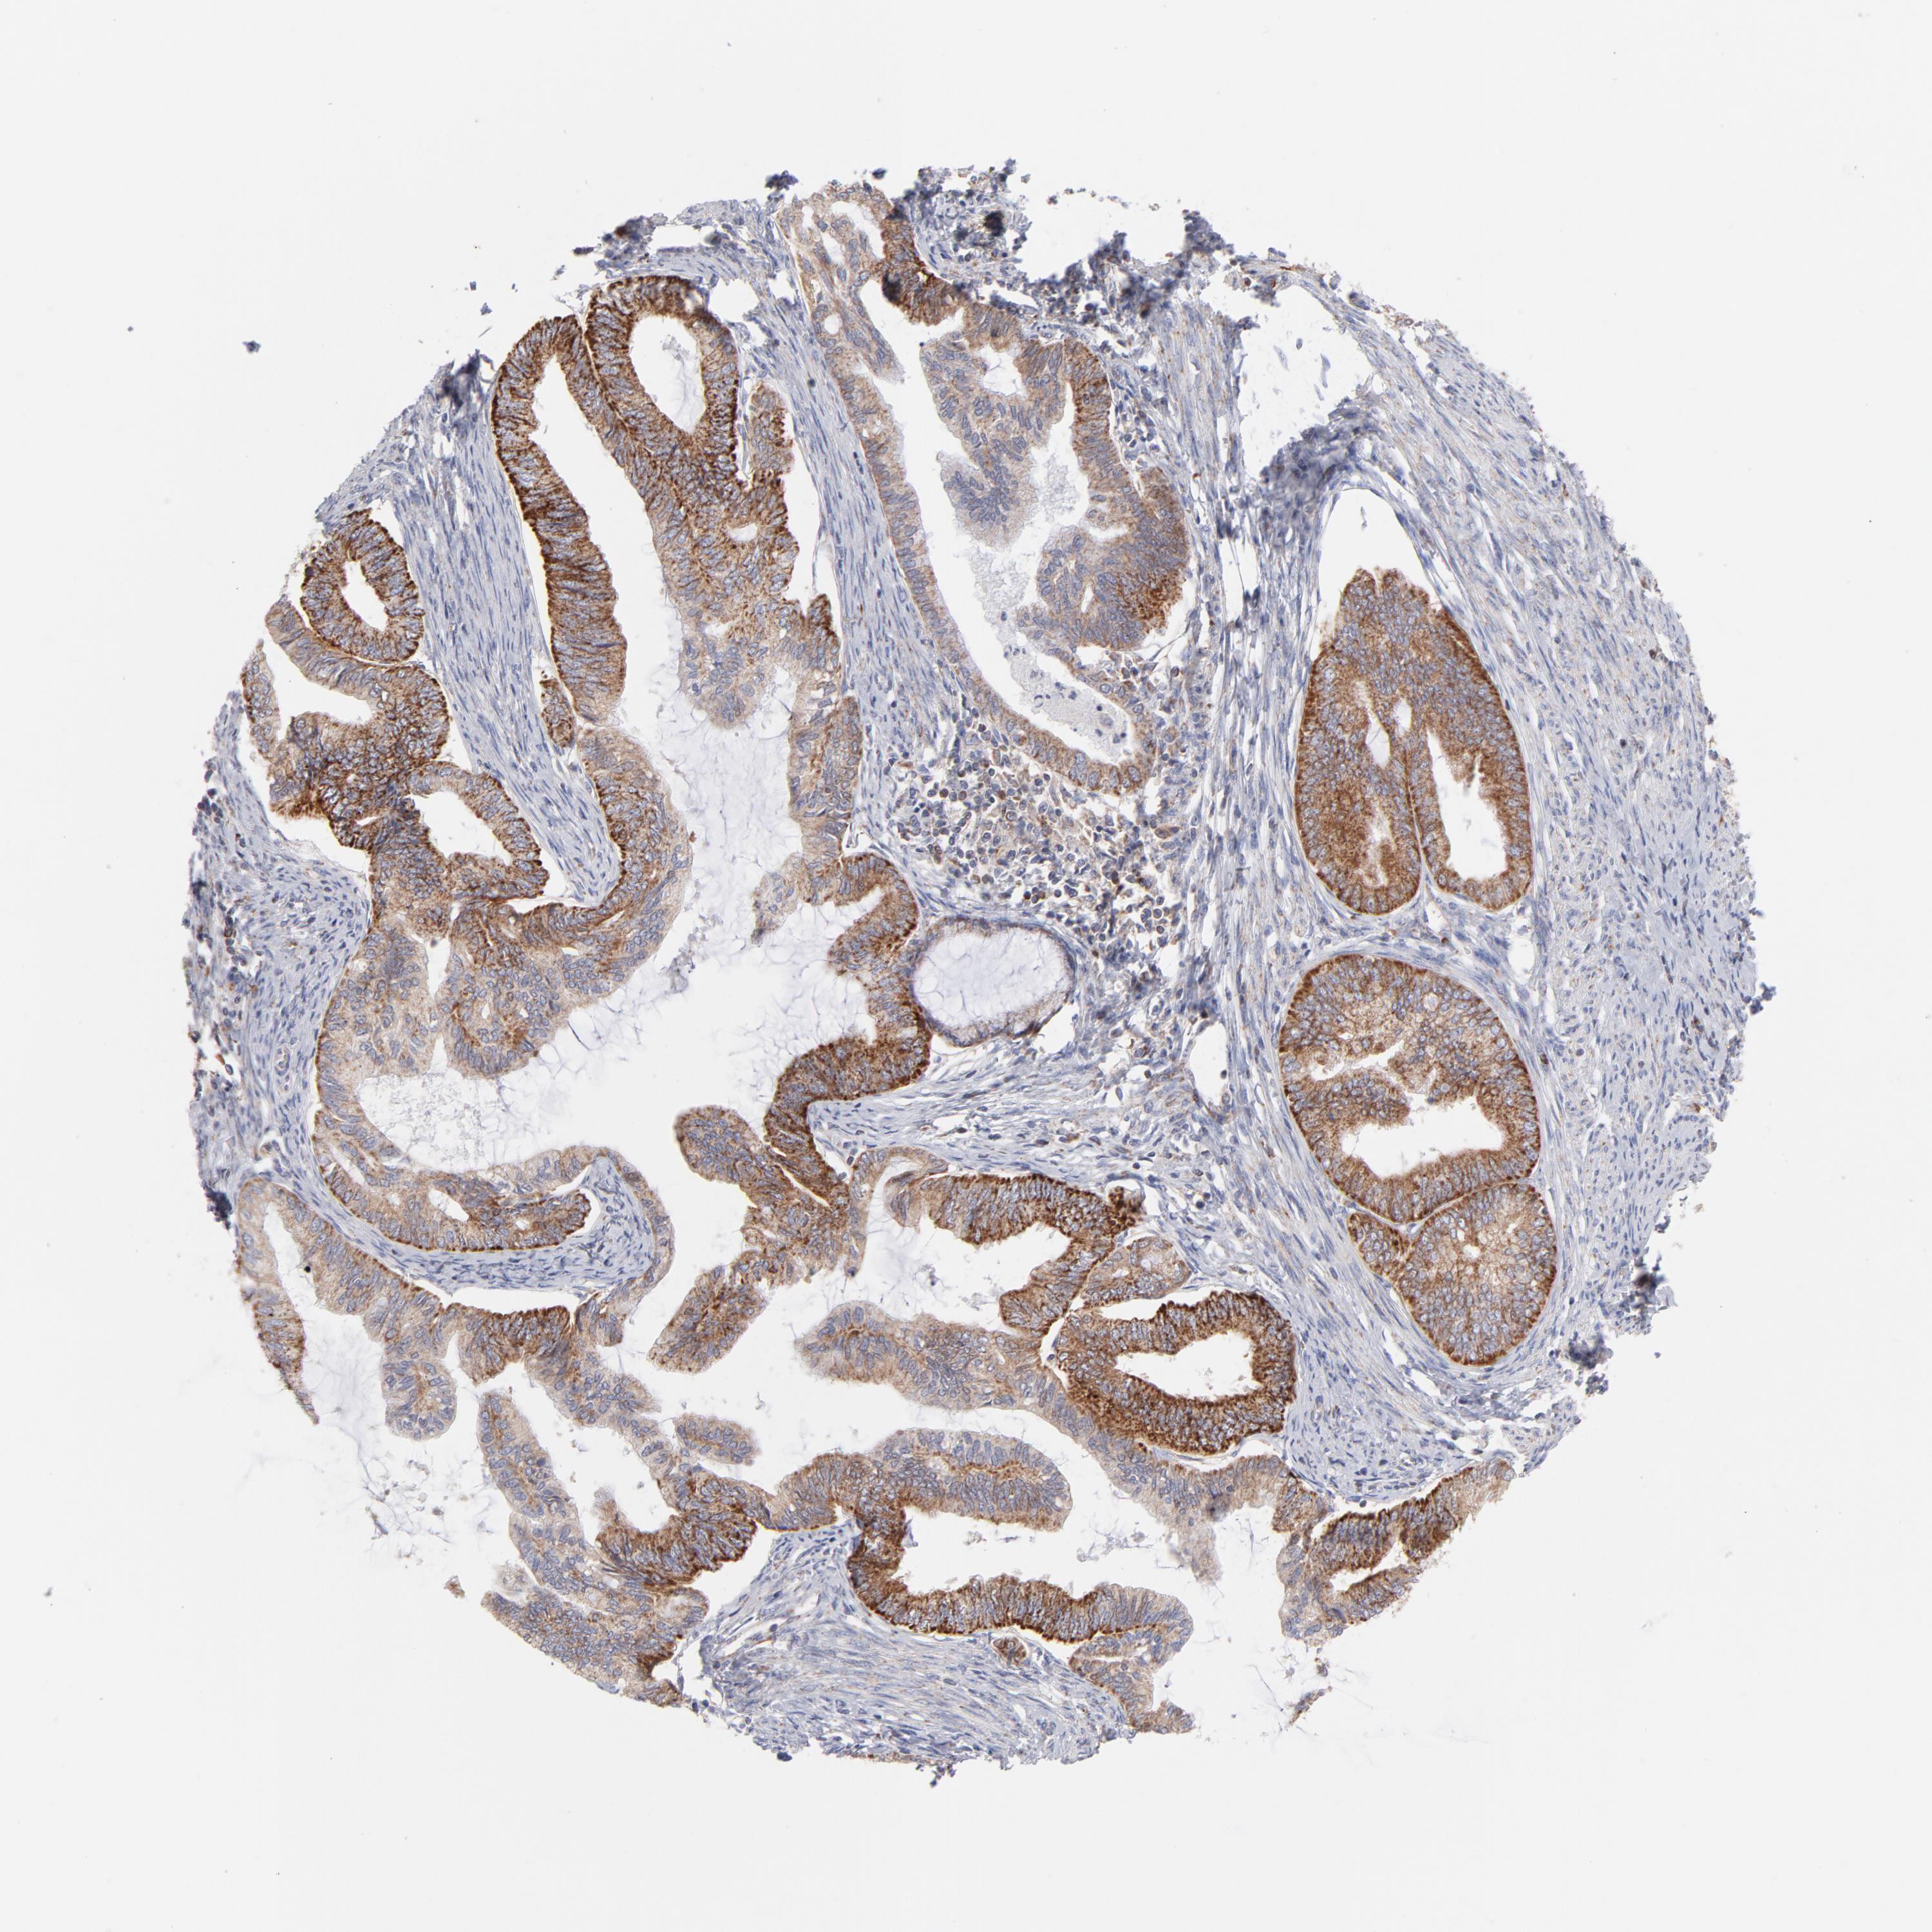

ENDOMETRIAL CANCER - Protein expressioni

A mouse-over function shows sample information and annotation data. Click on an image to view it in a full screen mode. Samples can be filtered based on level of antibody staining by selecting one or several of the following categories: high, medium, low and not detected. The assay and annotation is described here.

Note that samples used for immunohistochemistry by the Human Protein Atlas do not correspond to samples in the TCGA dataset.

Antibody stainingi

Antibody staining in the annotated cell types in the current human tissue is reported as not detected, low, medium, or high, based on conventional immunohistochemistry profiling in selected tissues. This score is based on the combination of the staining intensity and fraction of stained cells.

Each image is clickable and will lead to virtual microscopy that enables deeper exploration of all samples and also displays staining intensity scores, fraction scores and subcellular localization as well as patient and tissue information for each sample.

Antibody HPA003628

Staining

High

Medium

Low

Not detected

Intensity

Strong

Moderate

Weak

Negative

Quantity

>75%

75%-25%

<25%

None

Location

Nuclear

Cytoplasmic/membranous

Cytoplasmic/membranous,nuclear

Adenocarcinoma, NOS

Neoplasm, malignant, NOS